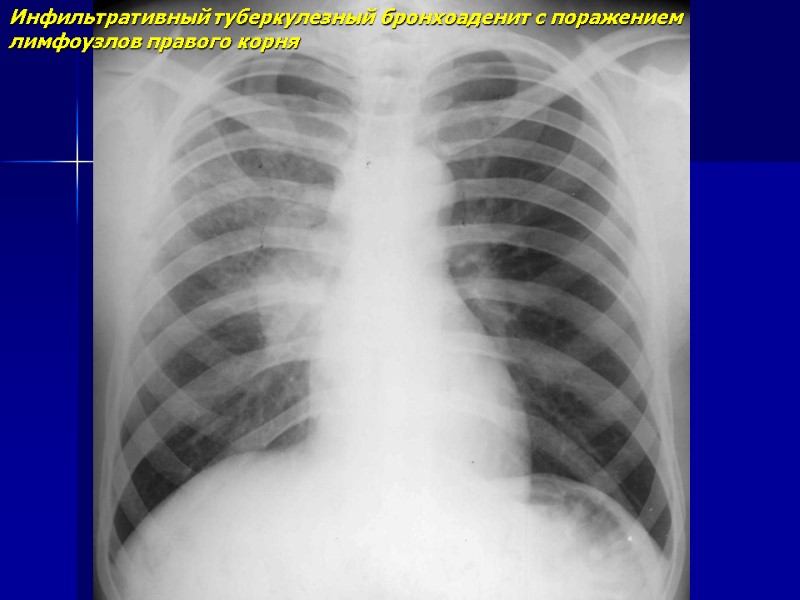

Инфильтративный туберкулезный бронхоаденит с поражением лимфоузлов правого корня

Инфильтративный туберкулезный бронхоаденит с поражением лимфоузлов правого корня